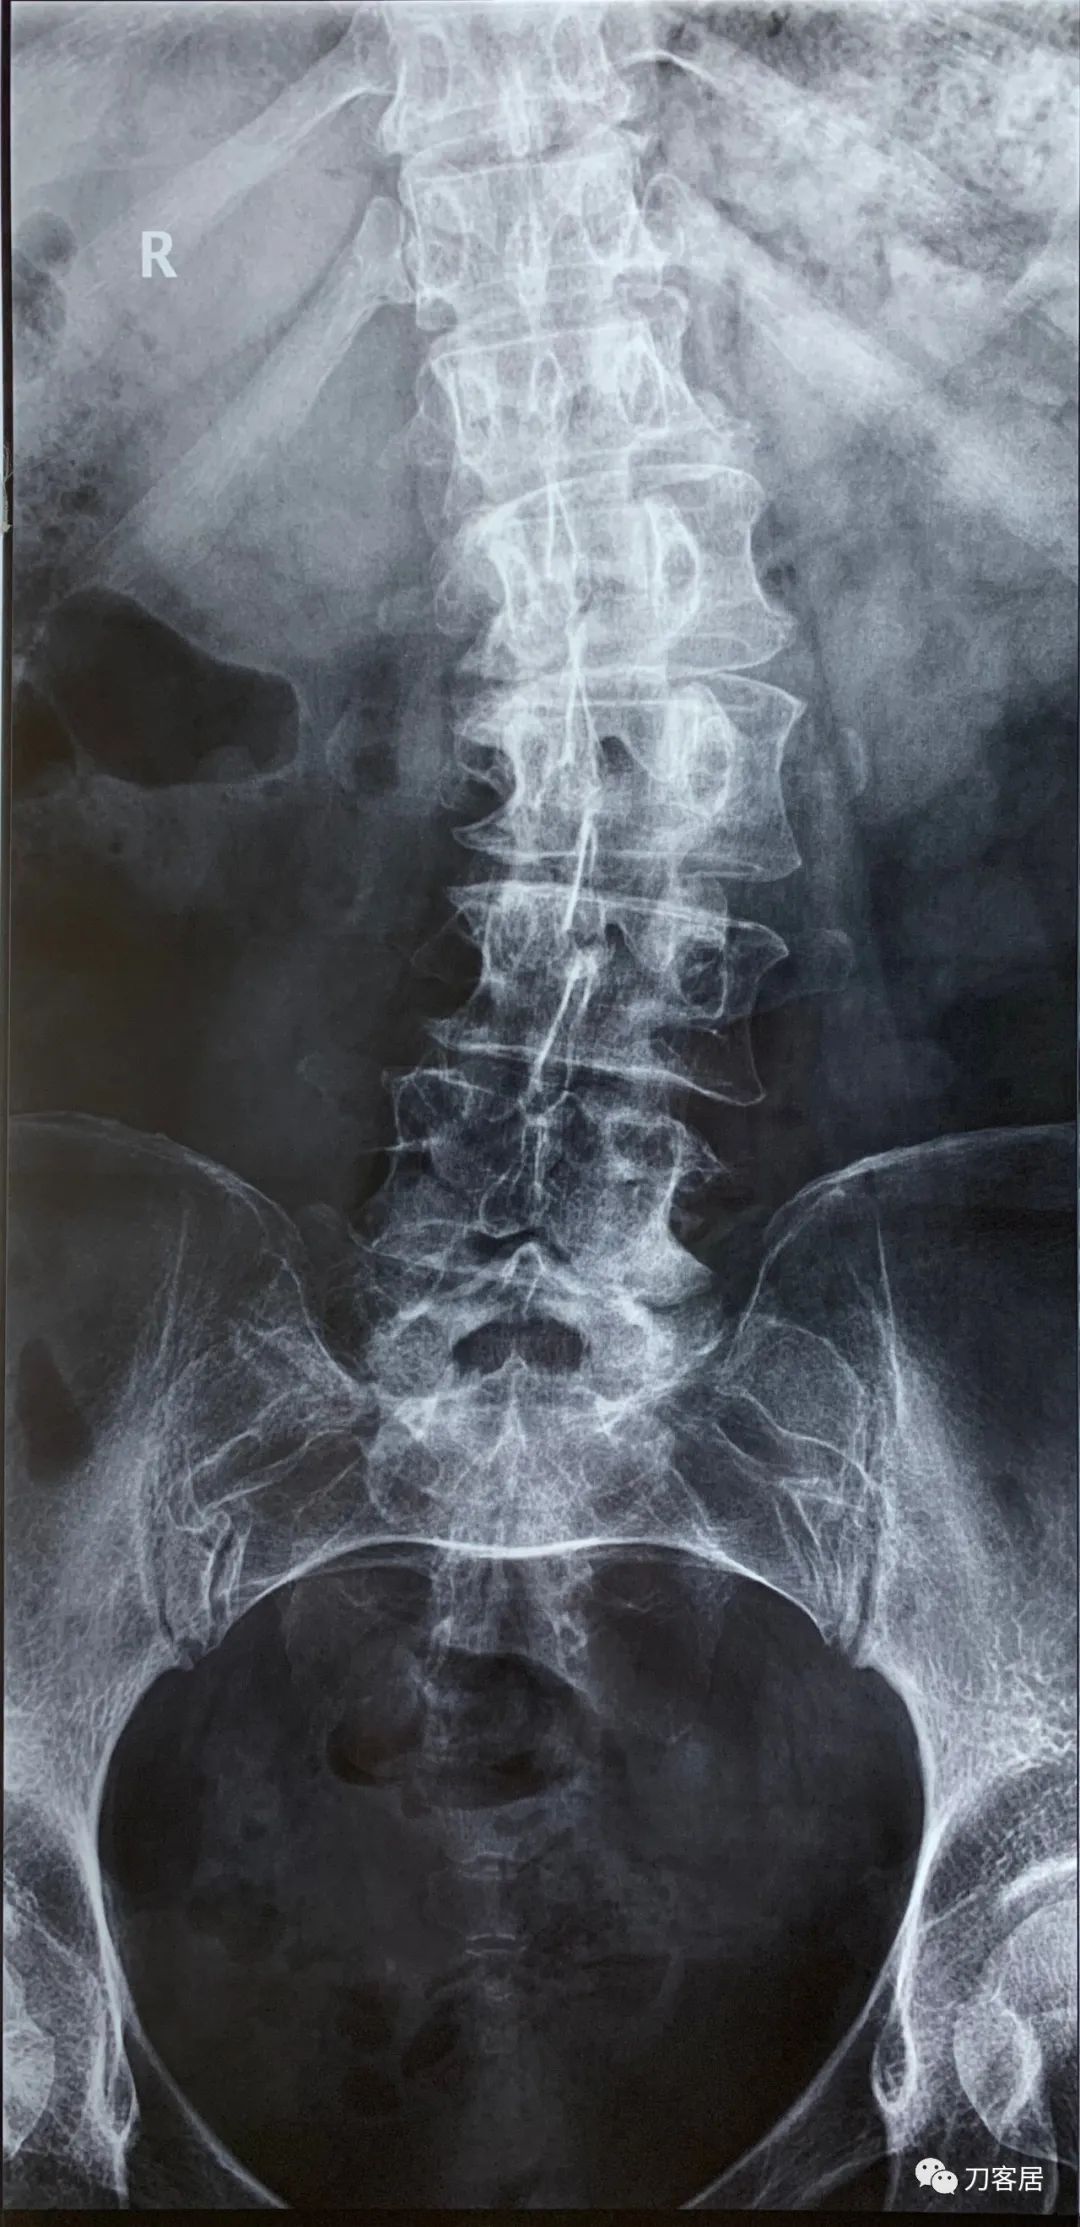

2021年5月17日,西京医院骨科门诊找我就诊,自带影像学检查资料提示腰椎侧弯,腰3-4,腰4-5椎间盘突出,黄韧带肥厚,椎管狭窄。

建议其查双光子骨密度,骨盆正位片以及腰椎间盘平扫。腰椎正侧位X线片以及动力位片,站立位脊柱全长正侧位X线片,以了解其是否有骨质疏松,并了解脊柱侧弯情况,腰椎局部X线表现情况和腰椎间盘突出和椎管狭窄情况。

从这个患者的影像资料分析,颈椎间盘突出问题不大,没有明确的上位神经元损伤表现,所以,不考虑颈椎和胸椎问题。腰椎侧弯畸形,但不严重。因为存在腰椎侧弯,使得腰椎MRI在扫描切面的时候,显示的椎间盘突出或椎管狭窄会有一定的误差,所以,又加做了经椎间盘的CT平扫,影像表现并不严重,综上,腰椎间盘突出,腰椎管狭窄,腰椎侧弯,不考虑手术治疗。同时,患者的主要痛苦是心理疾病,而不是器质性疾病,所以,以心身疾病治疗为主。虽然患者骨密度检查结果提示正常,但X线片显示骨质疏松,且其症状也与骨质疏松的症状有符合之处,比如静息痛,不能入睡,动作及姿势变换时痛加重等,所以,给予实验性抗骨质疏松治疗,以观疗效。